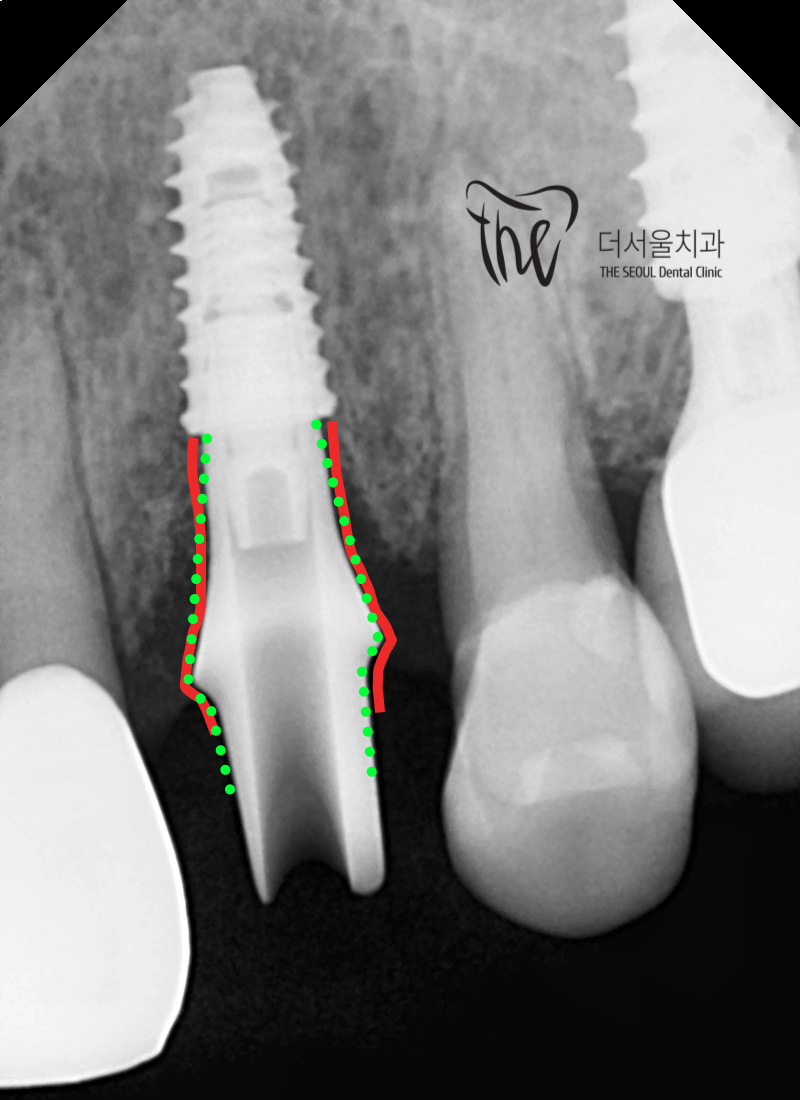

사진에서 볼 수 있는 것은 바로 임플란트 치료 를

할 때 뼈 속에 심겨지는 Implant fixutre 와

크라운을 연결시키는 어버트먼트 라는 겁니다.

근데, 제가 빨간색 및 초록색 점섬으로

표기를 해두었는데

해당 사진 속 어버트먼트는 정확히 말씀드리면

맞춤형 지대주, Customized abutment 라는

겁니다. 즉, 환자 개개인의 잇몸 높이나 뼈의

위치에 맞게 만들어진 세상에 1개 밖에 없는

기둥인 셈입니다.

빨간색으로 표기를 해둔 곳은, fixture level 로

부터 bone level 으로 이행되는 라인을 그린거고

굴곡이 져 있어서 환자의 구강 내 상태에

딱 맞게 만들어졌다는 것을 느끼실 수 있습니다.

툭 튀어나와있는 쪽은, gingival level 이라하여

잇몸의 높이까지 맞춘건데 초록색 점선은

제가 임의로 그린 위치입니다.